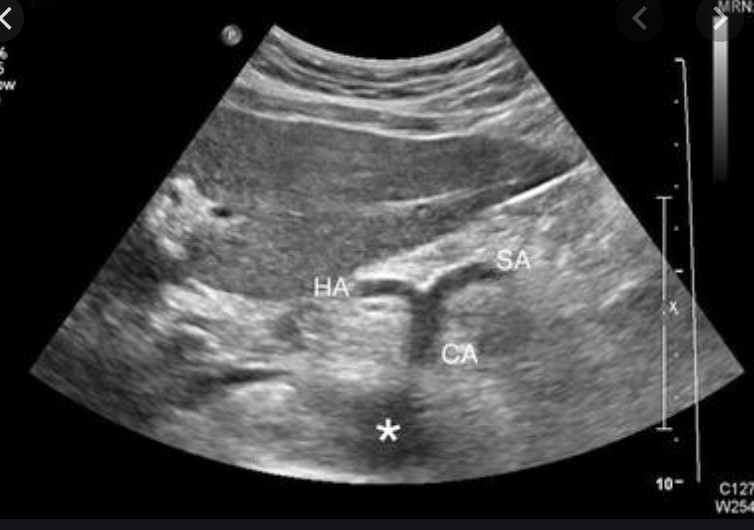

You should attempt to locate the major branches when ultrasounding to aid in proper identification and to ensure you are scanning the entire aorta. Obtain views of the celiac, SMA, and aortic bifurcation.

The celiac can be identified from the “seagull sign.” The celiac, hepatic artery, and splenic artery form a seagull shape.